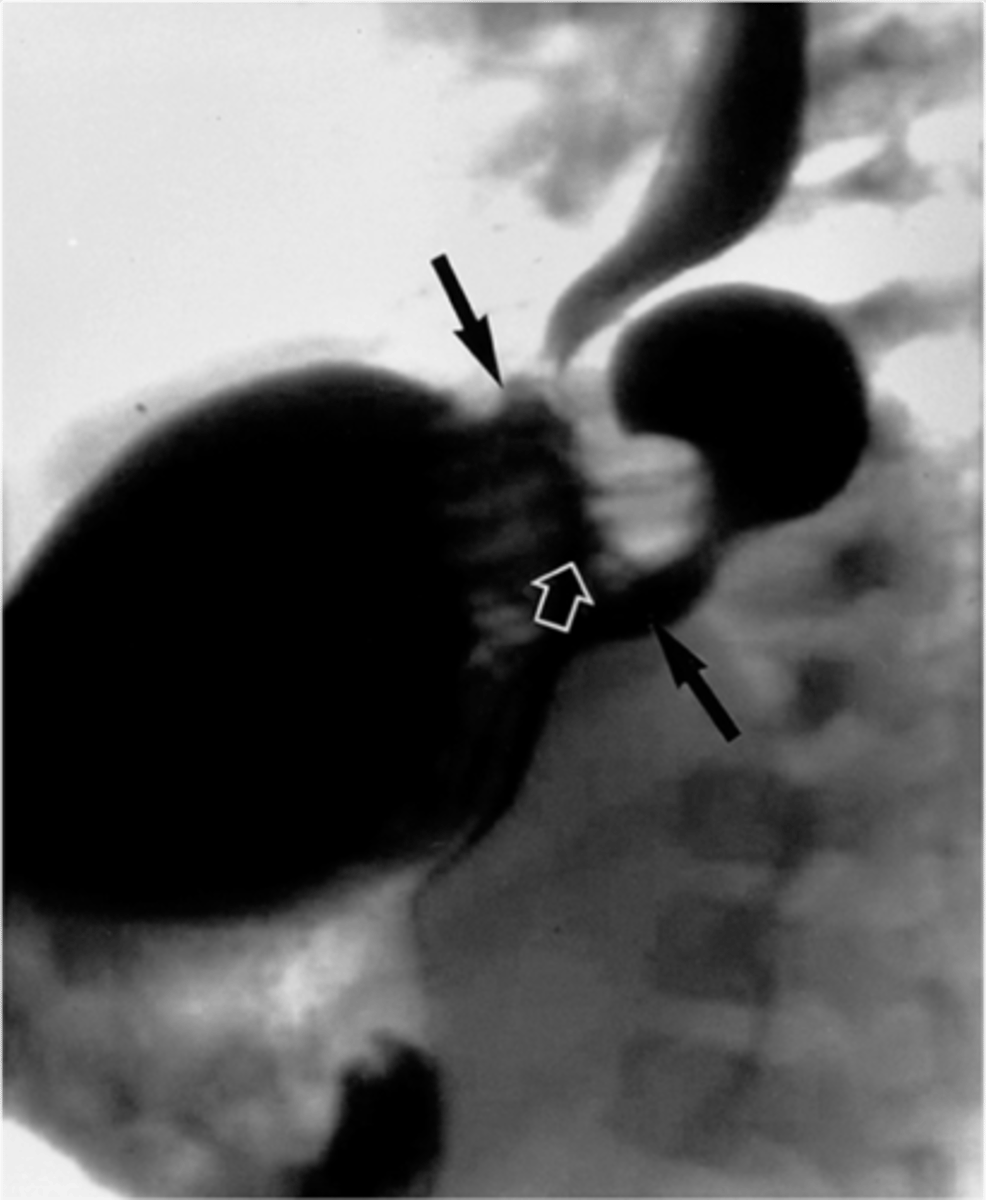

Sliding hiatal hernia

Sliding hiatal hernia (pic 2)

Sliding hiatal hernia (pic 3)